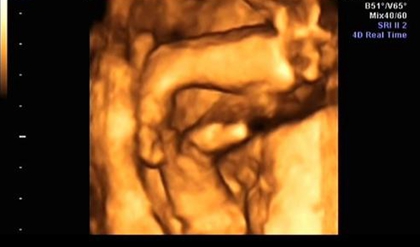

四维b超检查,确实需要宝宝配合,让宝宝动起来,通过四维b超动态的检测胎儿各个器官、皮肤与面部,所以很多网上的说法是女宝宝在做B超检查的时候更不容易配合,其实这种说法是没有依据的,宝宝在妈妈肚子里的时候会胎动,也会自己变换姿势,这是正常的,宝宝不配合和性别是没有关系的,如果做四维的时候想要让宝宝配合,那么就要想办法咯。

胎儿在4个月的时分就能够检测到性别了,但是精确率只要85%-90%,其中男宝宝的性器官比拟明显,精确率到达95%以上,而女宝宝的性器官并没有那么明显,精确率只要85%,当医生正在操作B超的时分,若宝宝正处于背部的姿态或手脚正好蜷到一同,从而遮挡了性别器官,这也会形成性别的改动,另外假如你家宝宝太调皮了,不太配合,姿态不对,医生也不可以很精确的看到Ta的生殖器,结果就没有那么精确了,所以四维还是有一定的概率会翻盘的。